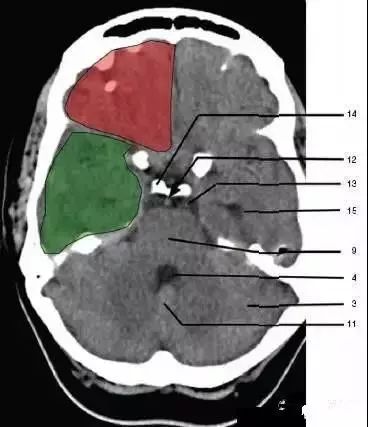

11、小脑蚓部(Cerebellar vermis)

12、基底动脉(Basilar artery)

13、桥前池(Prepontine cistern)

14、鞍背(Dorsum sellae)

15、侧脑室颞角(Temporal horn of lateral ventricle):绿色部分为颞叶(Temporal Lobe),浅红色部分为额叶(Frontal Lobe)

16、环池(Ambient cistern)